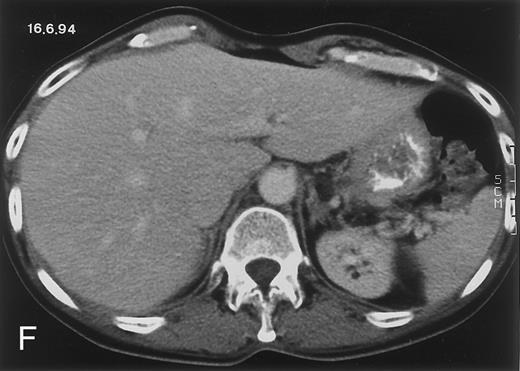

Radiologic evolution in patient A. (A) Postcontrast abdominal CT scan on March 16, 1993 shows multiple small hypodense areas in all segments of the liver, suggestive of hepatic candidiasis. Seven days previously, the patient had recovered from severe neutropenia after the first cycle of chemotherapy for AML. (B) On April 23, 6 days after the neutrophil count had dropped below 500/μL in the second cycle of chemotherapy, there is no evidence of focal lesions on postcontrast CT scan. (C) On June 18, when neutrophils were normalized for 46 days, CT scan again shows multiple small abscesses.

(D) On August 23, 15 days after the neutrophil count had dropped below 500/μL in the third chemotherapy cycle, focal liver lesions clearly decreased in size and number. (E) On September 30, 35 days after neutrophil recovery, multiple hepatic abscesses are seen (arrowhead). To show maximal extent of lesions the scan shown is at a slightly different level. (F) On June 16, 1994, 230 days after neutrophil recovery, the CT scan has normalized.